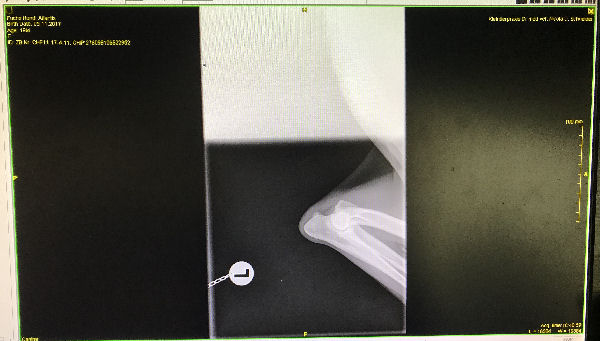

Atlantis - ED-Röntgen

img_5246 (1)-Atlantid-ed-links